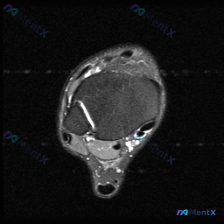

踝关节MRI看到软组织液,别只想到炎症,我梳理了完整鉴别思路

本次读片基于踝关节MRI-T2序列轴位图像,扫描层面为踝关节远端轴位,可清晰辨认胫骨、腓骨、距骨以及后方跟腱等正常解剖结构。T2序列对液体和水肿敏感,正常肌腱韧带应为低信号(黑色),液体/水肿为高信号(白色)。

问题是观察影像中软组织液相关改变,具体征象整理如下:

- 外侧韧带区域异常:图像左侧(腓骨侧)腓骨外侧及前方韧带结构不连续、模糊,伴随弥漫性高信号改变

- 腱鞘异常:腓骨后方踝关节周围软组织内可见管状、片状高信号,符合腱鞘积液表现

- 关节腔异常:踝关节前方及外侧关节间隙可见异常T2高信号,提示关节积液

- 软组织异常:踝关节外侧及前方皮下、深层软组织可见弥漫性高信号斑片影,提示软组织水肿